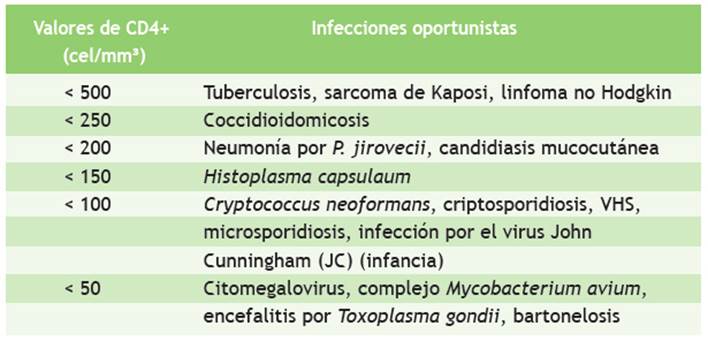

En la Tabla 1 se muestran los exámenes de laboratorio que se realizaron durante la hospitalización del paciente: baciloscopia en esputo con resultado negativo, baciloscopia en orina con resultado 5 BAAR y baciloscopia en heces que resultó positiva (+), ecografía torácica con reporte de líquido libre en ambos hemitórax, un volumen de 400 ml en el hemitórax izquierdo y 150 ml en el derecho; radiografía de tórax que muestra derrame pleural bilateral con predominio izquierdo (Figura 1); ecografía abdominal con hallazgos de esplenomegalia y nódulos hipoecogénicos (Figura 2); test de adenosina deaminasa en líquido pleural con valor 33. Los resultados de carga viral para VIH fueron 181 000 copias/ml y CD4: 63.

Tabla 1 Exámenes de laboratorio alterados tomados el día del internamiento

HCM: hemoglobina corpuscular media; CHCM: concentración de hemoglobina corpuscular media; TP: tiempo de protrombina; TTP: tiempo de tromboplastina parcial

En nuestro caso, el paciente fue sometido a una prueba sérica 5 días después del internamiento, y 3 días después recibió los resultados con un recuento de CD4+ con valor de 63; por lo que ingresa al rango de infecciones oportunistas que aparecen con valores de CD4+ entre 500 a 100 cel/mm3. Como se menciona en la Tabla 2, puede aparecer cualquier tipo de infección oportunista de ese rango, pero con mayor prevalencia a la aparición de criptosporidiosis, criptococosis, microsporidiosis e infección por virus del herpes simple (VHS), los cuales aparecen desde un recuento < 100 cel/mm3 11,12.